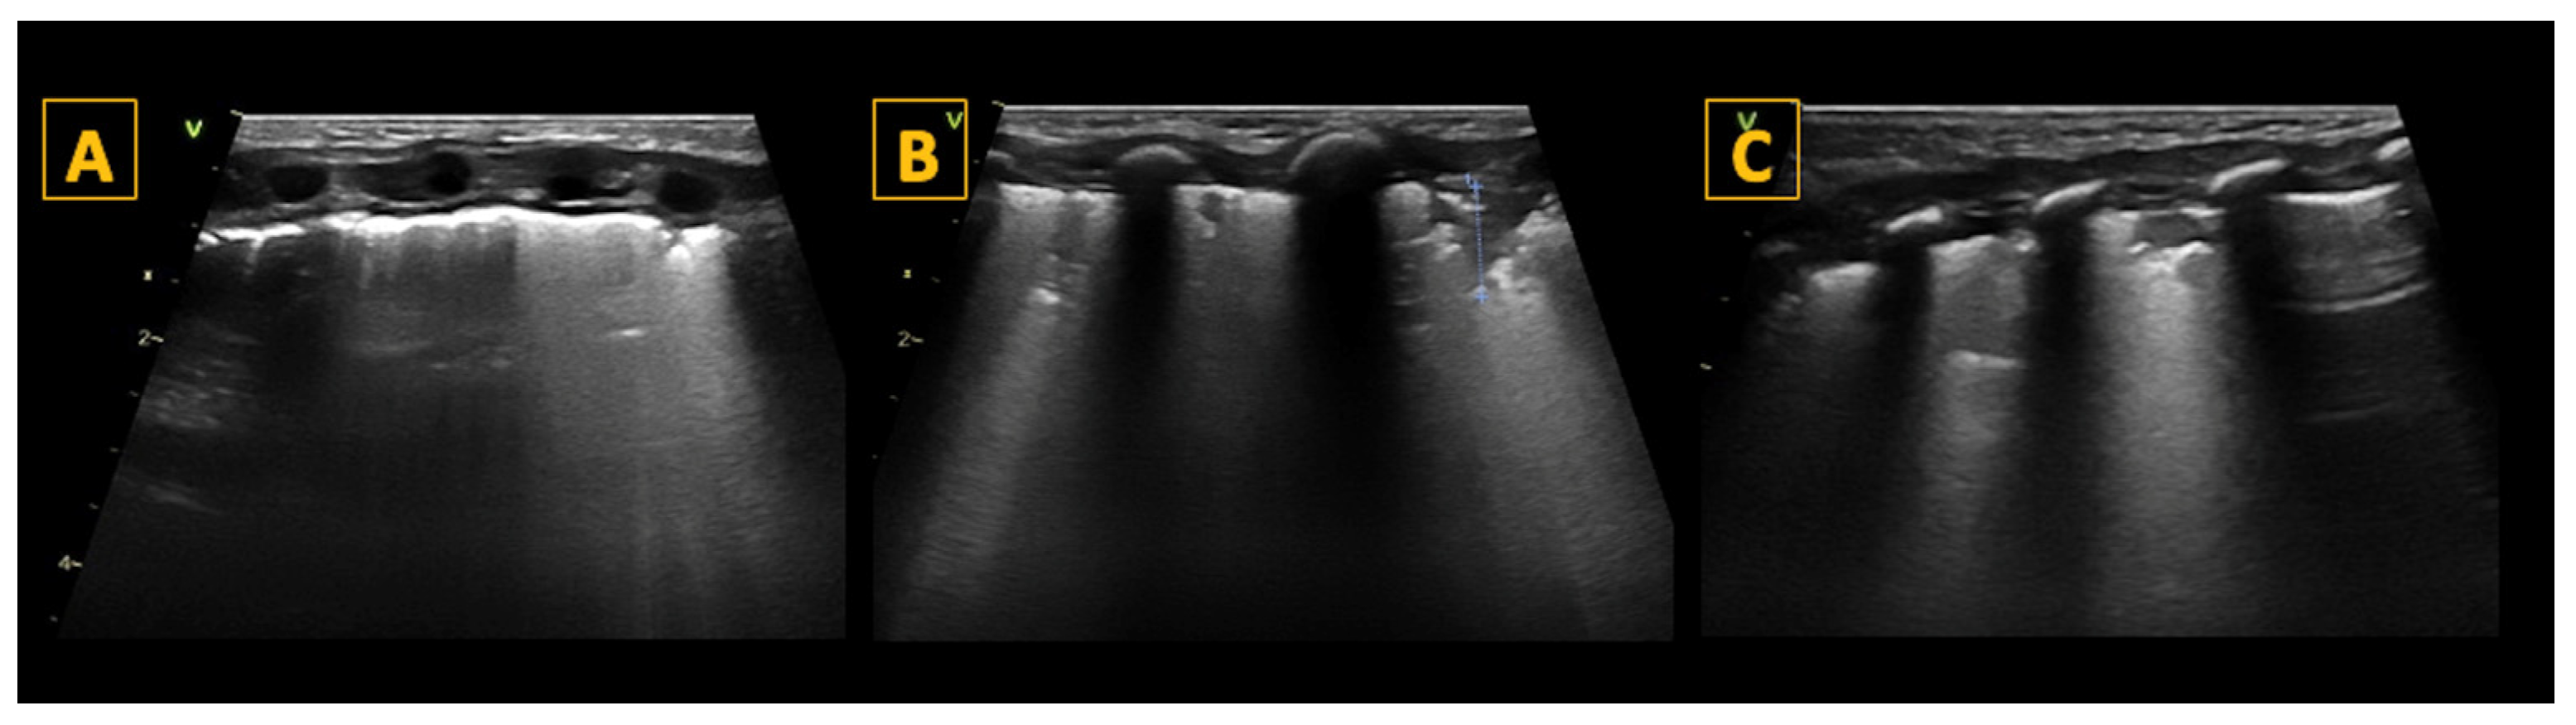

. R1 is the right upper anterior region, R2 is the right lower anterior region, R3 is right lateral, L1 is the left upper anterior region, L2 is the left lower anterior region, and L3 is left lateral, whilst RP and LP are the right and left posterior areas, respectively. The areas used for LUS are represented by red crosses in addition to the blue circles

and comprise R1, R2, R3 and L1, L2, and L3.